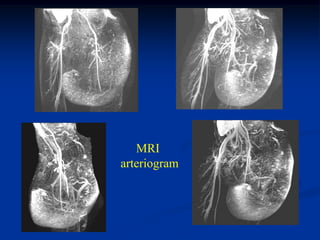

Case #1211.2               Synovial hemagioma knee

15 year male with knee pain for 6 months

Coronal T-1   Coronal T-2

Axial T-2

Surgical exposure at time of excisional biopsy

Case #1211.2 Synovial hemagioma knee 15 year male with knee pain for 6 months

• 363.

• 364.

• 365.

Surgical exposure attime of excisional biopsy